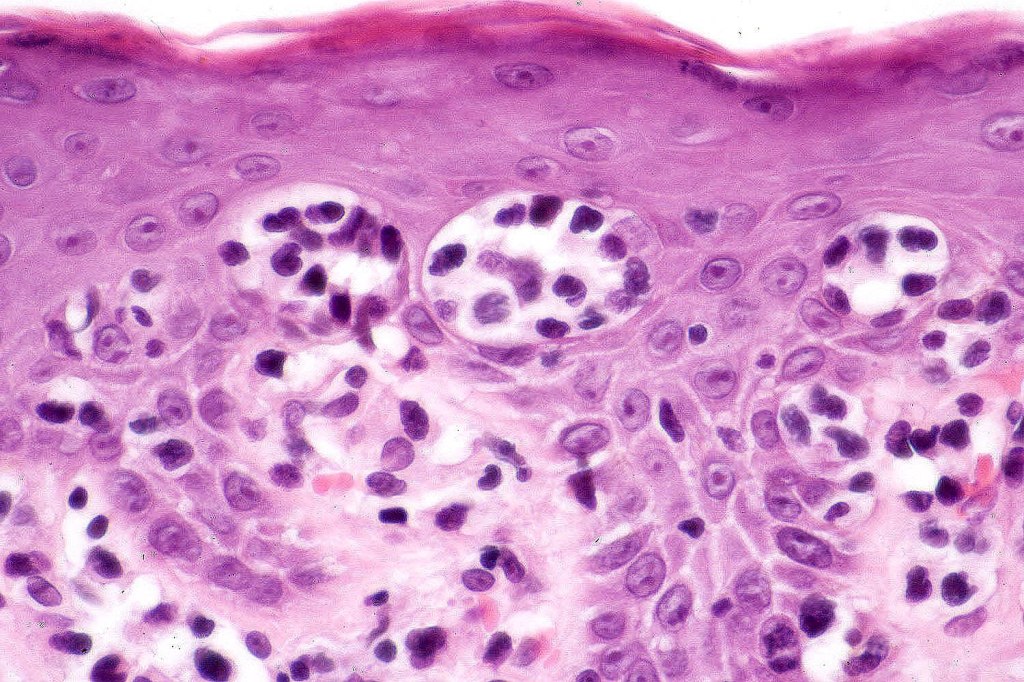

Histological features

The histological hallmark of mycosis fungoides is the presence of large atypical lymphocytes with a convoluted/cerebriform nuclear border (Sézary cells). These may be found at the epidermal-dermal jnuction and as collections within the epidermis (Pautrier microabscess). These are most easily found in plaque stage disease. The epidermal component can be subtle in patch stage disease and is often lost in tumor stage dsease. The classification into patch, plaque & tumor stage disease is less helpful histologically as the features merge from one to the other. It is all a matter of degree.

Plaque Stage Disease

•Compact hyperkeratosis & patchy parakeratosis

•Acanthosis

•Psoriasiform hyperplasia common

•Epidermotropism is often marked with conspicuous Pautrier microabscesses

•Lichenoid variant & poikiloderma atrophicans vasculare

•Variable folliculotropism (+/- mucinosis) & syringotropism

•Coarse collagen bundles in papillary dermis

•Superficial band-like dermal infiltrate of atypical lymphocytes, eosinophils, plasma cells & histiocytes